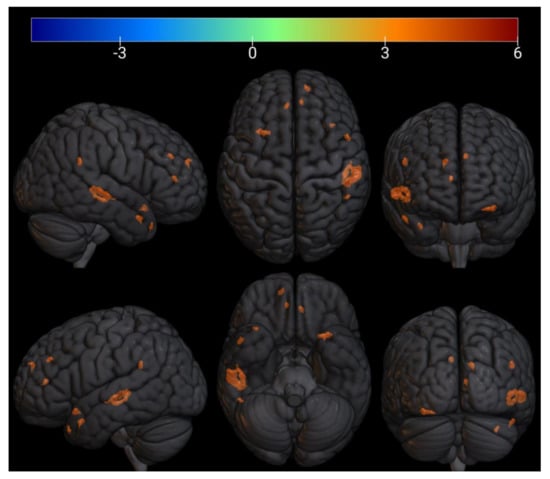

3.3. FMRI Analysis

| № Cluster | N Active Voxels in Cluster | Anatomical ROI | N Active Voxels in ROI | Peak MNI-Coordinates, mm | Peak T-Value | Peak p-Value | ||

|---|---|---|---|---|---|---|---|---|

| X | Y | Z | ||||||

| 1 | 27 | TP r (Temporal Pole) | 27 | 38 | 20 | −38 | 5.4 | 0.0002 |

| 2 | 3 | Cereb1 l (Cerebellum Crus1) | 3 | −36 | −60 | −36 | 4.9 | 0.0004 |

| 3 | 28 | TP r (Temporal Pole) | 28 | 54 | 8 | −24 | 5.5 | 0.0002 |

| 4 | 6 | Cereb1 l (Cerebellum Crus1) | 6 | −14 | −74 | −28 | 4.7 | 0.0005 |

| 5 | 11 | aPaHC r (Parahippocampal Gyrus) | 2 | 28 | −6 | −28 | 6.7 | 4.69 × 10−5 |

| Hippocampus r | 9 | |||||||

| 6 | 6 | aPaHC r (Parahippocampal Gyrus) | 1 | 30 | −14 | −26 | 6.1 | 8.75 × 10−5 |

| Hippocampus r | 5 | |||||||

| 7 | 7 | aPaHC l (Parahippocampal Gyrus) | 2 | −28 | −4 | −26 | 5.3 | 0.0002 |

| Amygdala l | 5 | |||||||

| 8 | 7 | Hippocampus l | 6 | −24 | −8 | −24 | 5.1 | 0.0003 |

| Amygdala l | 1 | |||||||

| 9 | 6 | pPaHC l (Parahippocampal Gyrus) | 6 | −20 | −24 | −20 | 5 | 0.0004 |

| 10 | 20 | aSTG l (Superior Temporal Gyrus) | 3 | −46 | −2 | −16 | 6 | 0.0001 |

| PP l (Planum Polare) | 17 | |||||||

| 11 | 32 | pPaHC r (Parahippocampal Gyrus) | 19 | 30 | −28 | −16 | 7.6 | 1.74 × 10−5 |

| pTFusC r(Temporal Fusiform Cortex) | 2 | |||||||

| Hippocampus r | 11 | |||||||

| 12 | 9 | pMTG r (Middle Temporal Gyrus) | 9 | 60 | −10 | −20 | 5.9 | 0.0001 |

| 13 | 64 | IC l (Insular Cortex) | 13 | −32 | 16 | −18 | 6.3 | 7.09 × 10−5 |

| FOrb l (Frontal Orbital Cortex) | 51 | |||||||

| 14 | 9 | TP r (Temporal Pole) | 9 | 46 | 14 | −18 | 5 | 0.0004 |

| 15 | 18 | Brainstem | 17 | −8 | −32 | −12 | 6.4 | 5.92 × 10−5 |

| Cereb45 l (Cerebellum 4 5) | 1 | −8 | −32 | −12 | ||||

| 16 | 8 | Hippocampus l | 8 | −24 | −26 | −12 | 5.9 | 0.0001 |

| 17 | 6 | aSTG r (Superior Temporal Gyrus) | 5 | 60 | 0 | −16 | 4.4 | 0.0008 |

| aMTG r (Middle Temporal Gyrus) | 1 | |||||||

| 18 | 3 | Brainstem | 3 | 10 | −28 | −12 | 5 | 0.0004 |

| 19 | 240 | pSTG r (Superior Temporal Gyrus) | 122 | 60 | −24 | −2 | 7.2 | 2.58 × 10−5 |

| pMTG r (Middle Temporal Gyrus) | 118 | |||||||

| 20 | 10 | Thalamus r | 2 | 12 | −32 | −4 | 6.9 | 3.63 × 10−5 |

| Brainstem | 8 | 12 | −32 | −4 | ||||

| 21 | 5 | LG l (Lingual Gyrus) | 5 | −26 | −60 | −2 | 5.5 | 0.0002 |

| 22 | 17 | FP r (Frontal Pole) | 17 | 38 | 56 | −2 | 6 | 0.0001 |

| 23 | 39 | OP r (Occipital Pole) | 39 | 10 | −98 | 14 | 6.7 | 4.27 × 10−5 |

| 24 | 22 | toMTG r (Middle Temporal Gyrus) | 9 | 62 | −40 | 4 | 5.6 | 0.0002 |

| pSMG r (Supramarginal Gyrus) | 13 | 62 | −40 | 4 | ||||

| 25 | 5 | toMTG r (Middle Temporal Gyrus) | 4 | 50 | −38 | 4 | 4.8 | 0.0005 |

| pSMG r (Supramarginal Gyrus) | 1 | |||||||

| 26 | 9 | ICC l (Intracalcarine Cortex) | 9 | −14 | −74 | 8 | 6 | 5.91 × 10−5 |

| 27 | 7 | PaCiG l (Paracingulate Gyrus) | 7 | −14 | 46 | 6 | 5.5 | 0.0002 |

| 28 | 26 | PaCiG r (Paracingulate Gyrus) | 13 | 10 | 42 | 12 | 5.1 | 0.0003 |

| AC (Cingulate Gyrus) | 13 | 10 | 42 | 12 | ||||

| 29 | 5 | AC (Cingulate Gyrus) | 5 | −4 | 36 | 18 | 5 | 0.0003 |

| 30 | 11 | FP r (Frontal Pole) | 11 | 26 | 54 | 20 | 5.3 | 0.0002 |

| 31 | 9 | Cuneal r (Cuneal Cortex) | 2 | 8 | −88 | 22 | 4.8 | 0.0005 |

| OP r (Occipital Pole) | 7 | |||||||

| 32 | 37 | Precuneous (Precuneous Cortex) | 3 | −4 | −76 | 28 | 5.9 | 0.0001 |

| Cuneal l (Cuneal Cortex) | 34 | −4 | −76 | |||||

| 33 | 21 | pSMG r (Supramarginal Gyrus) | 1 | 50 | −46 | 26 | 7.2 | 2.54 × 10−5 |

| AG r (Angular Gyrus) | 20 | 50 | −46 | 26 | ||||

| 34 | 7 | FP l (Frontal Pole) | 5 | −20 | 44 | 22 | 4.8 | 0.0005 |

| 35 | 51 | FP r (Frontal Pole) | 50 | 14 | 54 | 26 | 6.5 | 5.62 × 10−5 |

| SFG r (Superior Frontal Gyrus) | 1 | 14 | 54 | 26 | ||||

| 36 | 15 | AG r (Angular Gyrus) | 15 | 62 | −50 | 22 | 4.6 | 0.0006 |

| 37 | 24 | SFG l (Superior Frontal Gyrus) | 1 | −6 | 40 | 32 | 5.9 | 0.0001 |

| PaCiG l (Paracingulate Gyrus) | 23 | −6 | 40 | 32 | ||||

| 38 | 3 | sLOC r (Lateral Occipital Cortex) | 3 | 44 | −64 | 34 | 4.5 | 0.0008 |

| 39 | 14 | Precuneous (Precuneous Cortex) | 14 | 16 | −46 | 42 | 5.3 | 0.0003 |

| 40 | 9 | SFG r (Superior Frontal Gyrus) | 6 | 26 | 28 | 48 | 4.6 | 0.0006 |

| MidFG r (Middle Frontal Gyrus) | 3 | 26 | 28 | 48 | ||||

| 41 | 26 | SFG l (Superior Frontal Gyrus) | 26 | −10 | 14 | 62 | 6 | 9.75 × 10−5 |

| 42 | 10 | SFG r (Superior Frontal Gyrus) | 10 | 12 | 18 | 68 | 4.6 | 0.0006 |

| 43 | 8 | PreCG l (Precentral Gyrus) | 8 | −6 | −26 | 58 | −7.8 | 0.00001 |

| 44 | 4 | PostCG r (Postcentral Gyrus) | 4 | 16 | −32 | 74 | −4.5 | 0.0008 |